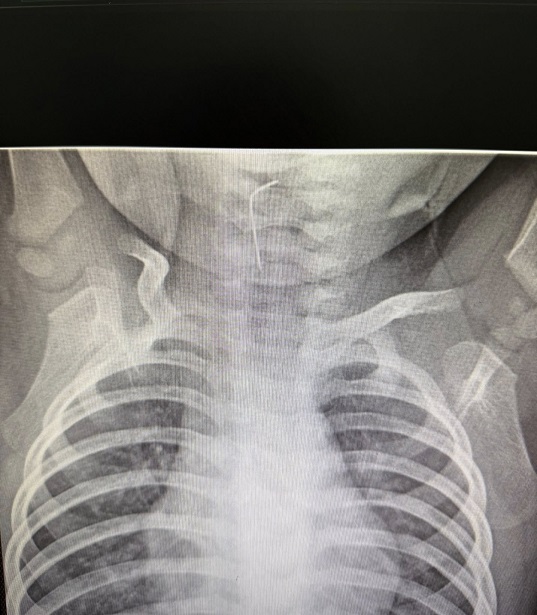

Белгілі болғандай, сәби абайсызда ине жұтып қойған. Тез арада аурухана мамандары — хирург Темірбеков Мұхагали және эндоскопист Ырысқұлов Бабыр эндоскопиялық әдісті қолдана отырып, рентгенологиялық тексеру жүргізді. Нәтижесінде бөгде заттың нақты орналасқан орнын анықтап, өңеште тұрып қалған бөгде затты сәтті түрде алып шықты.